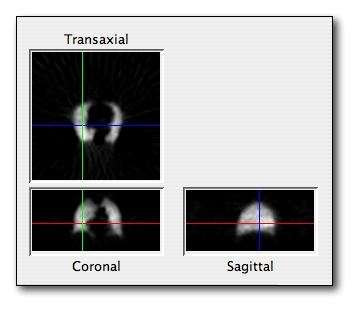

- Coronal and sagittal reconstructions are referred to as Orthogonal MPRs because the perspectives generated are from planes of image data which are at right angles to each other. Composite MPR displays can be generated so that linked cursors or crosshairs can be used to locate a point of interest from all three perspectives, as illustrated in these images:

|

|

- This form of image presentation is sometimes referred to as a TCS display - implying the viewing of Transaxial, Coronal and Sagittal slices. It can be combined with the slice projection methods we discussed earlier, as illustrated in the two sets of images below, where the blue lines highlight the limits of the coronal projections: